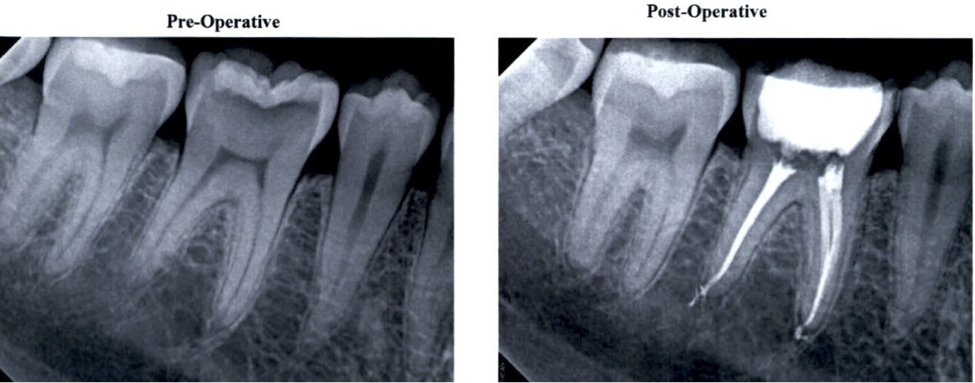

Root Canals www.thousandoaksfamilydentistry.comroot canal before after ray percha gutta canals tooth infection highlighting bright shape second shows left white

Root Canal Treatments | Precision Dental precisiondental.coPeriapical X-rays Before And After Root Canal Treatments. (a

Periapical x-rays before and after root canal treatments. (a www.researchgate.netRoot Canal Removal | Root Canal | Lakefront Family Dentistry